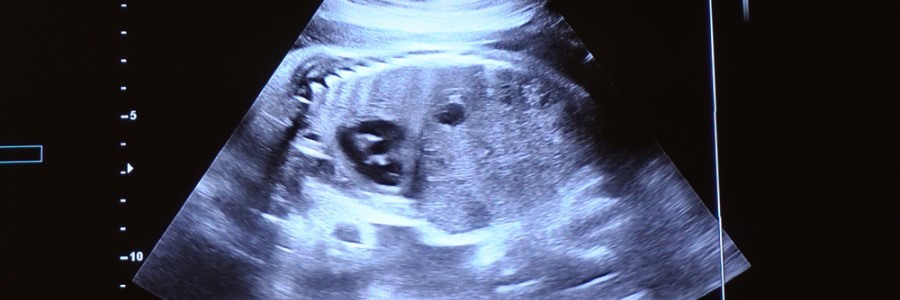

Una vez que el gel se ha aplicado, se moverá el transductor por la superficie de la piel. En ocasiones, el ultrasonido también se utiliza en la vagina o el recto para observar los ovarios, pólipos o las estructuras internas por si hay algún tipo de crecimiento o actividad anormal que sea útil para el diagnóstico. Las ondas sonoras se convierten en imágenes en tiempo real que se pueden ver en un ordenador. Estas se muestran en blanco y negro.

El motivo por el que el ultrasonido se utiliza tanto en el ámbito de la medicina en la actualidad es porque se trata de una técnica que es poco invasiva, segura para las madres que esperan un bebé y rápida en el momento de detectar masas anómalas que requieran de una intervención y abordaje tempranos.